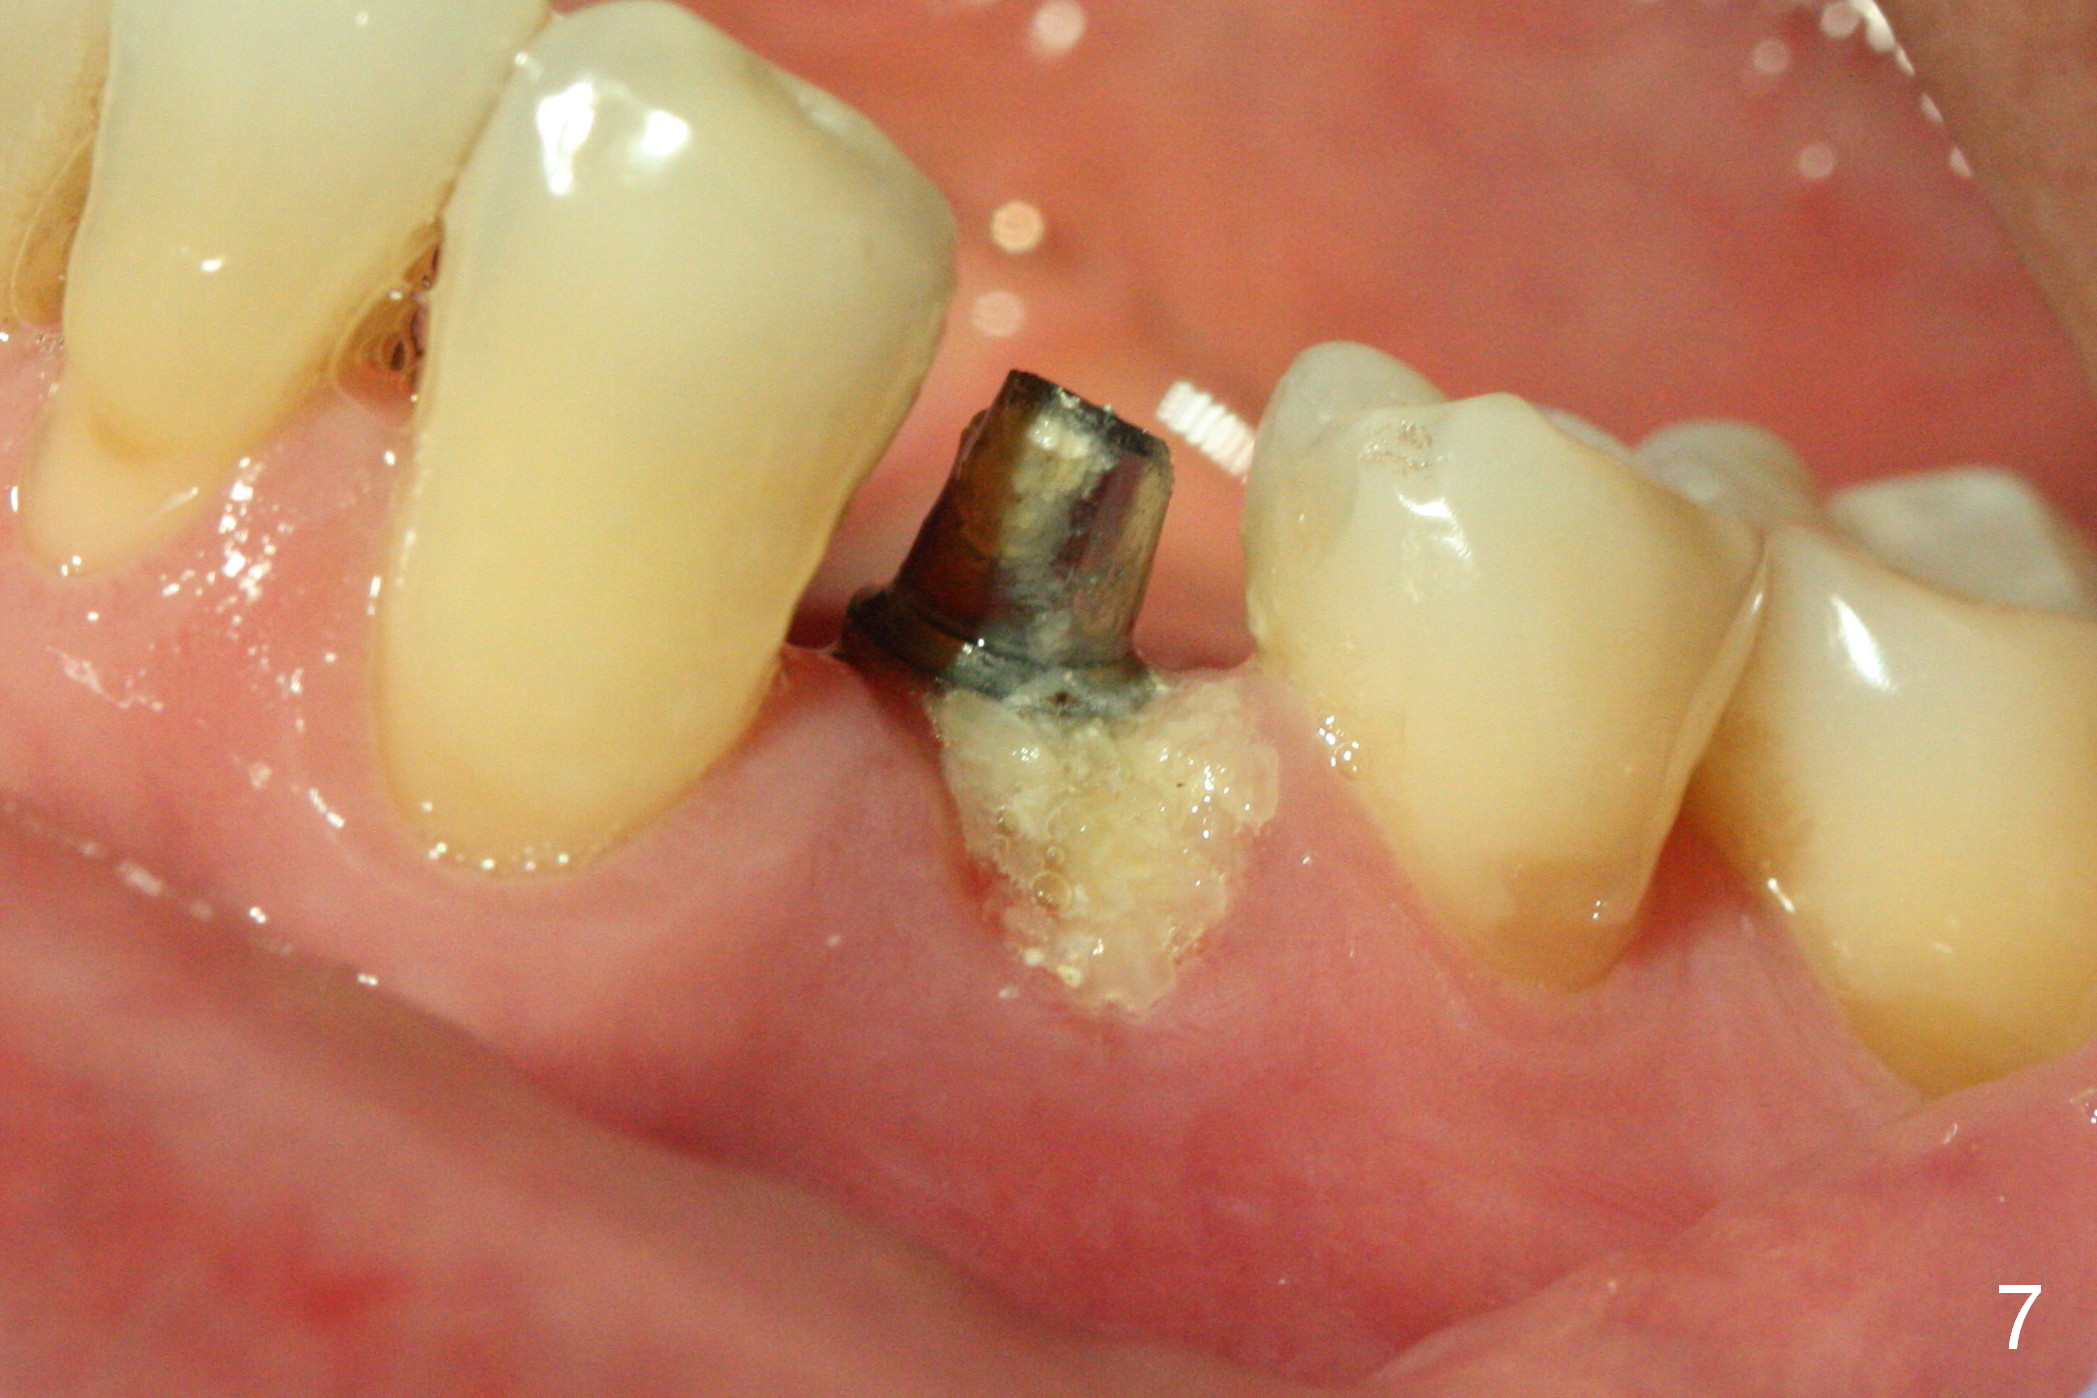

The residual root at #21 seems to be buccally positioned (Fig.1 *). The initial osteotomy is established with the 1.6 mm drill at 11 mm (Fig.2). Later the depth increases to 13 mm. The initial osteotomy is found to be too lingual, but experience shows that as osteotomy increases in diameter, the trajectory would shift buccally due to the thick lingual plate (slope). When 3.3 mm Magic drill reaches 11 mm, the patient feels pain. It is probably due to the dense bone. A 4x11 mm IBS implant cannot be seated due to high torque; it is removed. The osteotomy is increased with 3.8 mm drill. The implant is re-seated with >55 Ncm; it is over-lingually placed. Due to failure to seat the implant driver completely, the implant cannot be un-torqued. A 4.5 mm 15° angled abutment (3 mm cuff) is placed for immediate provisional (Fig.3,4 *).